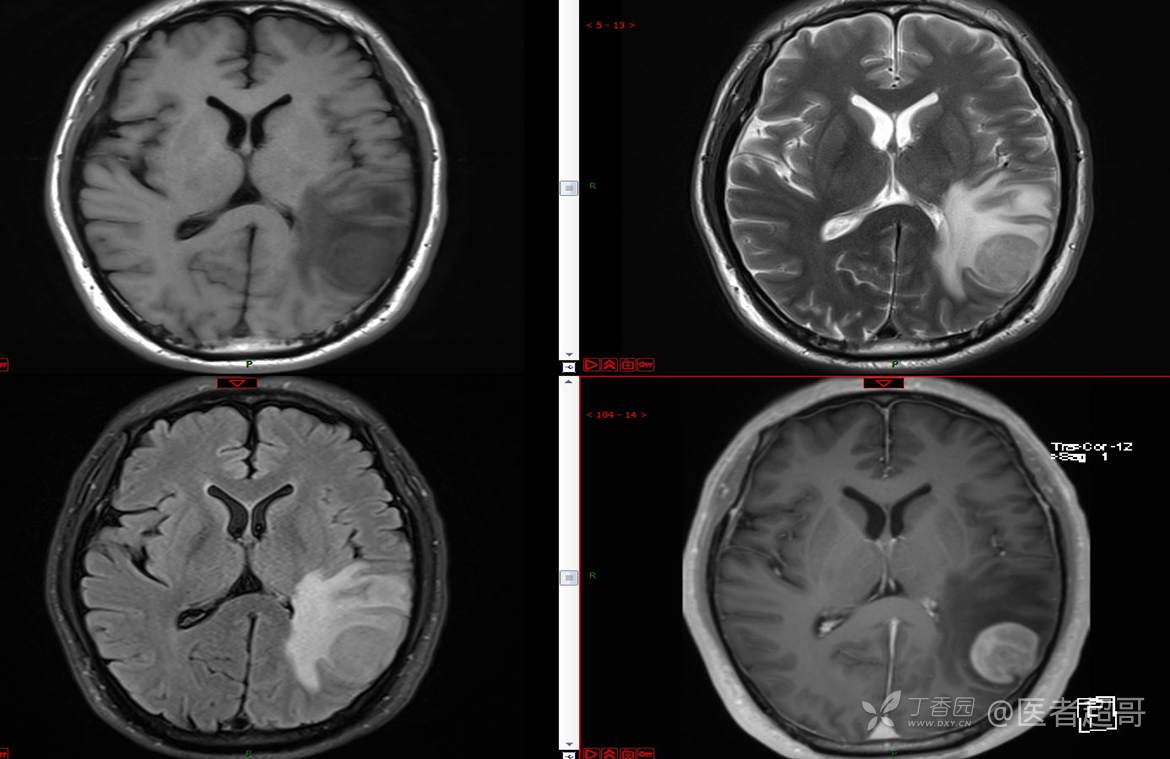

比较典型病例,CT、MRI齐全,请分析,领丁当!

男,56岁

主 诉:查体发现颅内占位10天。

现病史:患者于约10天前于我院查体时行颅脑MRI提示左侧顶叶占位病变,无头痛头晕,无恶心呕杜,无肢体活动不利,无感觉异常,现患者为求进一步治疗,就诊于我科门诊,门诊以“颅内占位性病变”收入我科。患者自发病以来,神志清,精神可,饮食及睡眠差,大小便无明显异常,体重无明显变化。